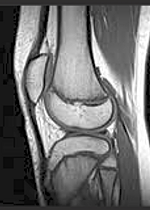

Adolescents And ACL Injuries: Current Research And Future ...

With the growing popularity of youth team sports such as soccer and basketball, there has been a substantial increase in the number of athletic injuries among adolescents. ... View Document

AllSports Medicine - Anterior Cruciate Ligament (ACL) Injury ...

Hello my name is Dr. Drew Warnick, and I am the surgical director of AllSports Medicine at All Children's Hospital. I am a pediatric orthopaedic surgeon with special training in pediatric and adolescent sports medicine. In this video, we are going to discuss Anterior Cruciate Ligament ... View Video